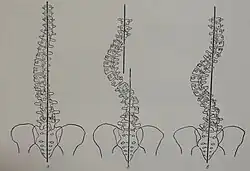

Delayed development of motor milestones as loss of ambulatory capacity is usually more severe in the congenital type 1A or MDC1A.[1][5] Skeletal muscle weakness is a characteristic feature. It more evident in the proximal muscles of the extremities. Facial and neck weakness have also been reported.[6] Scoliosis is a side curvature or abnormal deviation of the spine with an element of rotation. Scoliosis is usually rigid and progressive. It may be accompanied by lordosis.[7]

The clinical orthopedic features of congenital type 1A (MDC1A) in terms of type, distribution, laterality, deformity progression, chronological order of muscle and joint involvement etc., have shown a fairly characteristic pattern.[7] This is important to the differential diagnosis of LAMA2-MD and other subtypes of congenital muscular dystrophies among others.[7] LAMA2-MD especially MDC1A, usually manifests in progressive contractures of large joints like knees, ankles, elbow and hips. Contractures tend to be bilateral. That is involving both the left and right sides.[7] Observing the chronological order of development of joint contractures, namely early versus late in the disease course, could offer differential diagnostic clues for congenital muscular dystrophies as MDC1A, LMNA-Related muscular dystrophy among other genetic muscle diseases.[7][8][9] Of note, any unique clinical orthopedic features of LAMA2-MD should be put into context with the other clinical features, characteristic brain and muscle imaging, muscle immunostaining and genetic testing findings. An International retrospective early natural history study of LAMA2-MD proposed a classification based on motor or ambulatory capacity in which patients who attain the ability to sit and remain seated are classified as LAMA2-MD1 or LAMA2-RD1 and those who attain the ability to walk independently are classified as LAMA2-MD2 or LAMA2-RD2.[10] A study on a large series LAMA2-MD patients showed that bone mineral density was reduced in all adults and most children. Fragility fractures were reported occasionally.[6]